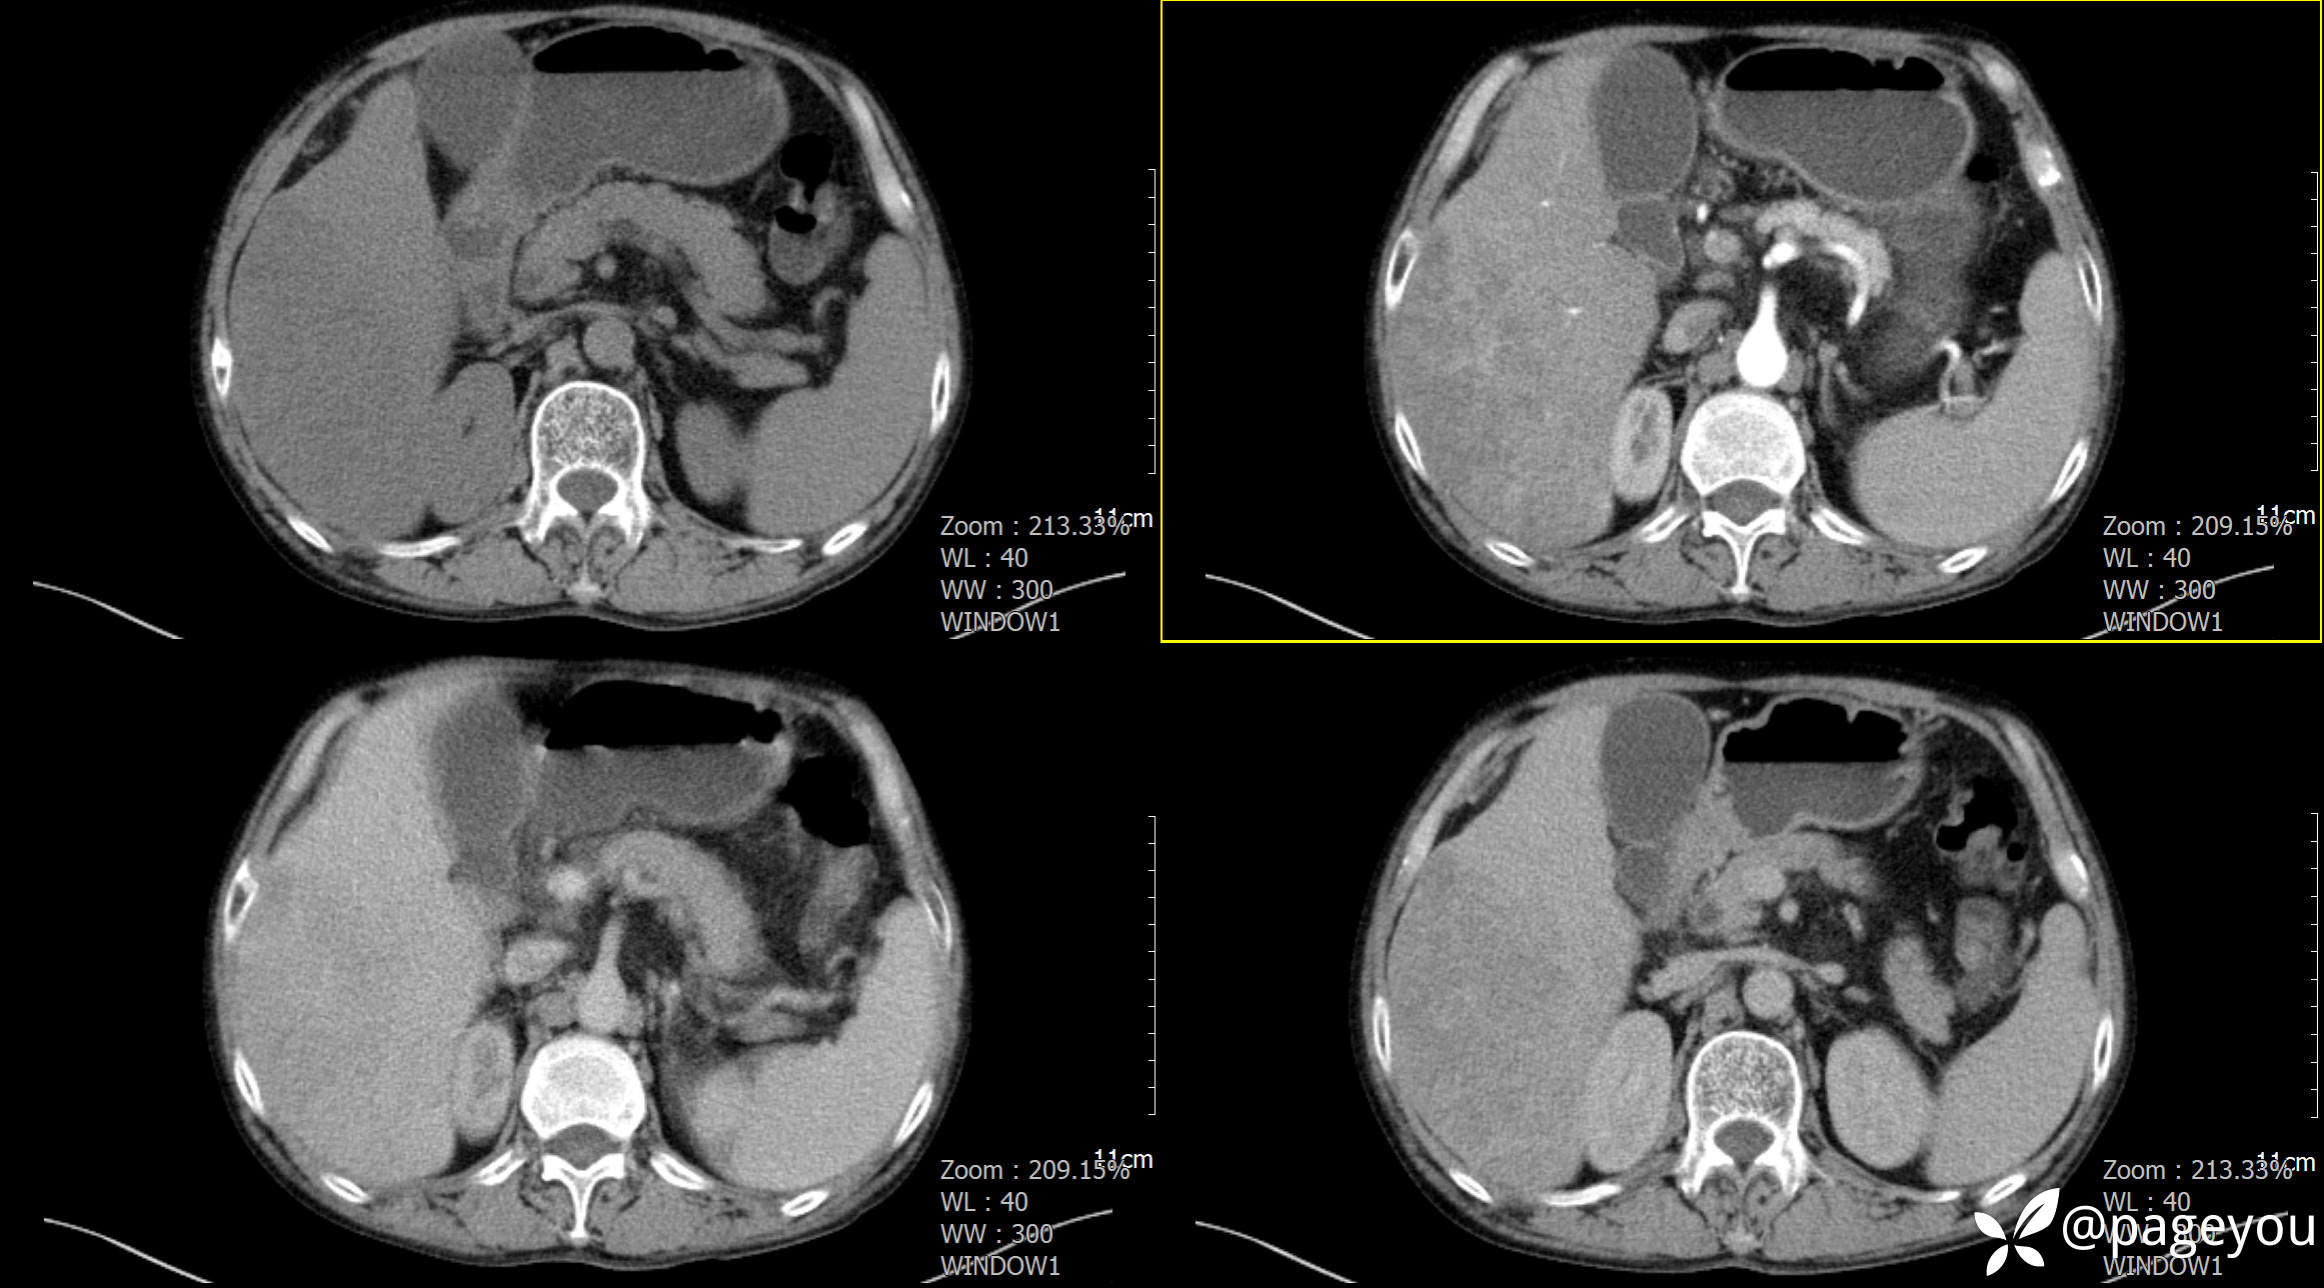

CT检查: